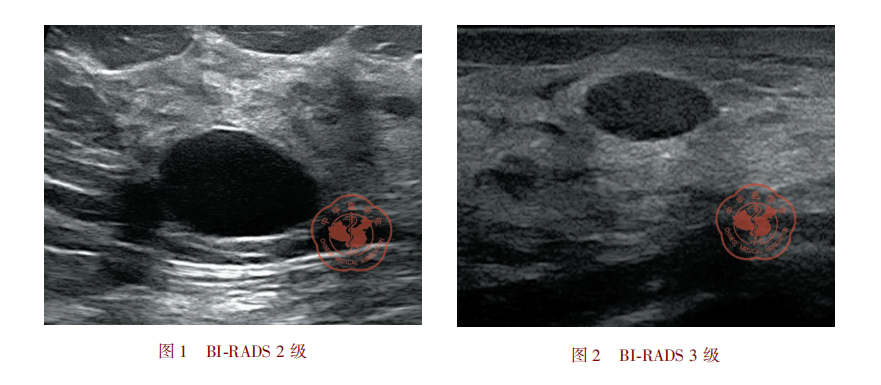

临床工作中,经常会有女性问我:“朱医生,我结节是良性的纤维腺瘤,可以不管它吧?”,或者也经常会碰到有些女性朋友隔2-3年才来复查一次乳腺的结节……类似这种情况还是很多见的,因为很多女性认为“纤维腺瘤是良性的,无害的,无需治疗”。但我想告诉大家的真相是:“纤维腺瘤虽然是良性的,但并非无害”,因为纤维腺瘤也会癌变!下面是我最近碰到的一个典型的病例。女性,32岁,发现双乳肿块5年余,定期复查中。此次超声检查发现右乳5点可见一大小约11×7mm、边界清楚的低回声病灶,血供也不丰富,与半年前大小无明显的变化。但仔细观察该病灶时,我发现这个结节内部可见多发的小片状囊性回声(图1)、质地硬(图2),与常规纤维腺瘤的超声表现不相符(纤维腺瘤一般为实质性病灶,内部无囊性成分,弹性软)。因为担心有癌变的危险,我将该结节的级别上调为BI-RADS4A类,建议手术活检。最后她的手术结果也证实了我的判断:“纤维腺瘤,其中见小灶小叶原位癌伴Paget样播散(局限于纤维腺瘤内),散在微钙化”。看到这里,可能很多女性朋友就开始担心自己的乳腺结节会不会癌变了,在此,我想告诉大家以下三点: 一、纤维腺瘤癌变发病率很低(0.002%-0.125%),多数是导管原位癌(DCIS)和小叶原位癌(LCIS)。瑞金医院良性病例手术约6000台/年以上,每年碰到纤维腺瘤癌变的病例不到10例。 二、若纤维腺瘤癌变,乳腺超声、钼靶或磁共振会有相应地恶性征象,例如囊性变、钙化、肿块突然快速长大等等,因此定期复查就非常重要了。 三、复查间隔时间:根据美国放射学会ACR制定的BI-RADS(BreastImagingReportingandDataSystem)指南,BI-RADS3类结节初次随访间隔通常是6个月,如果6个月检查中病灶稳定,推荐第二次6个月内短期随访检查,如第二次随访检查结果还是稳定的可将随访的间隔再延长。 总之,若您真的有乳腺腺瘤腺瘤,不要过度的担心,也不要毫不在意,定期复查非常重要且是必须的。在复查过程中,医生会根据您病灶的变化情况给出相应地处理意见。